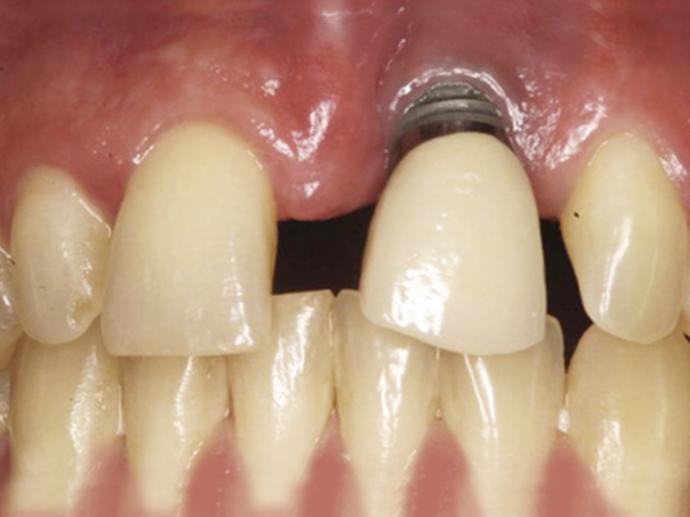

- 高解析AI斷層掃瞄儀:完整顯示骨質狀況及重要神經血管,使植牙都在最安全、最穩固的位置。

ALL ON全口重建是由4-6 顆植體(依條件而定)成,專為多顆缺牙或全口無牙患者設計的創新全口重建技術,僅需4-6 支植體即可支撐一整排固定式假牙,大幅減少手術次數與成本,並縮短療程時間。